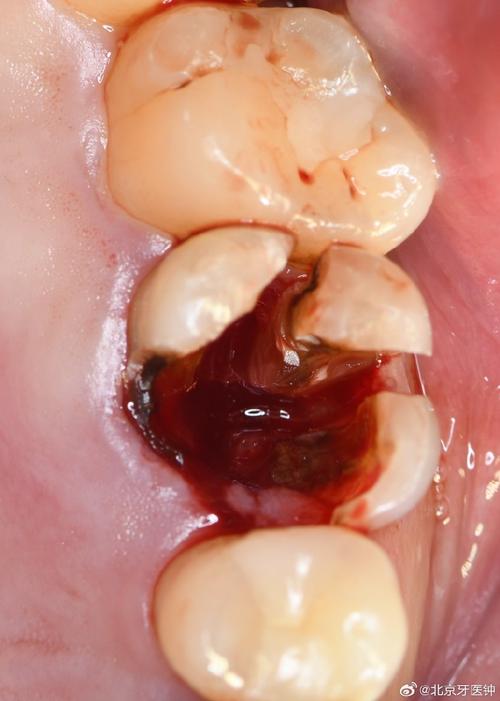

种植体植入(30-60分钟)

在局部麻醉下,医生切开牙龈,暴露牙槽骨,使用专用钻逐级备洞,将纯钛种植体精准植入预定位置,种植体表面通常有特殊处理(如喷砂酸蚀),以促进骨结合,术后需压迫止血24小时,遵医嘱服用抗生素预防感染,1周内避免手术区咀嚼,拆线后可恢复正常饮食(避免过硬食物)。